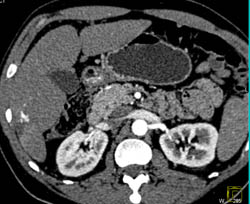

Portal Vein Aneurysm